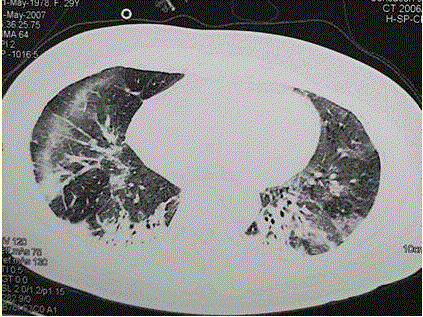

问题  患者女,29岁。间断干咳10年余,加重4个月,伴进行性呼吸困难1个月。病程中出现双手及双足非凹陷性肿胀、双侧膝关节及双侧肘关节对称性肿痛,面部出现细小红色丘疹。体检:T 36.5℃,P 88次/min,R 22次/min,BP 110/75 mmHg,SpO 93%(自然)。额部、前胸及后背散在红色小丘疹,双肺呼吸音增强,双肺中下肺野可闻及爆裂音,右肺明显。胸部CT 如图所示。 该患者最可能的诊断是(提示 患者无发热,血常规正常,痰培养阴性。)

选项 A、结节病 B、社区获得性肺炎 C、结缔组织病肺受累 D、肺部恶性肿瘤 E、军团菌肺炎 F、特发性间质性肺炎 G、肺泡蛋白沉积症

答案 C